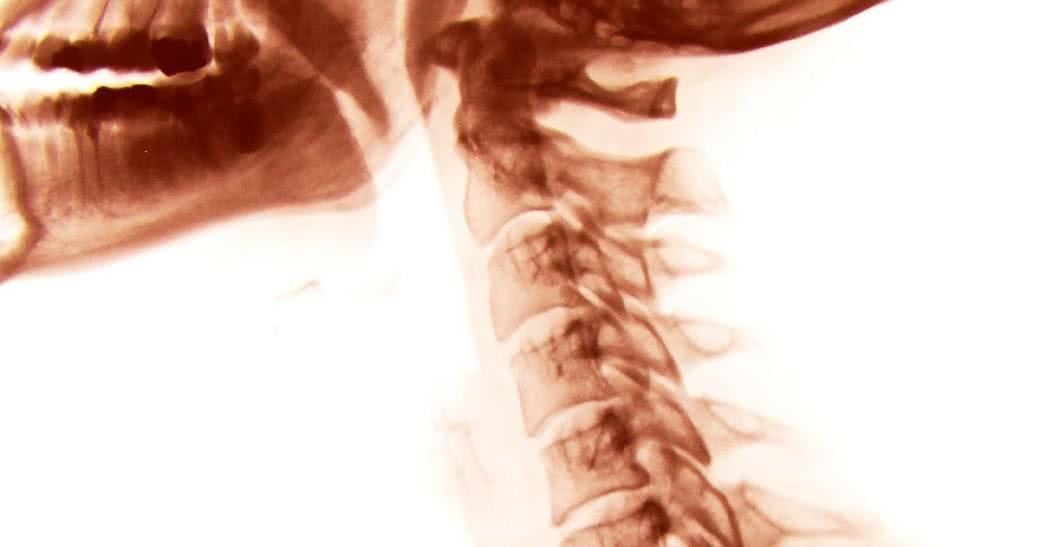

Prześwietlenie - lepiej nie dla dzieci

Lepiej nie robić zdjęć rentgenowskich dzieciom - twierdzą naukowcy. Promieniowanie emitowane podczas rutynowych badań radiologicznych zębów może mieć szczególnie zły wpływ na młody organizm.

Prześwietlenie szczęki, zębów i jamy ustnej może mieć zły wpływ na wciąż jeszcze rozwijające się narządy i tkanki – mówi grupa stomatologów, która chce zmienić standardową praktykę.

Dzieci powinny być poddane badaniu radiologicznemu tylko wtedy, gd y jest to absolutnie konieczne. Dawka promieni powinna być minimalna, a dziecku należy koniecznie zasłonić miejsce, w którym ma tarczycę.